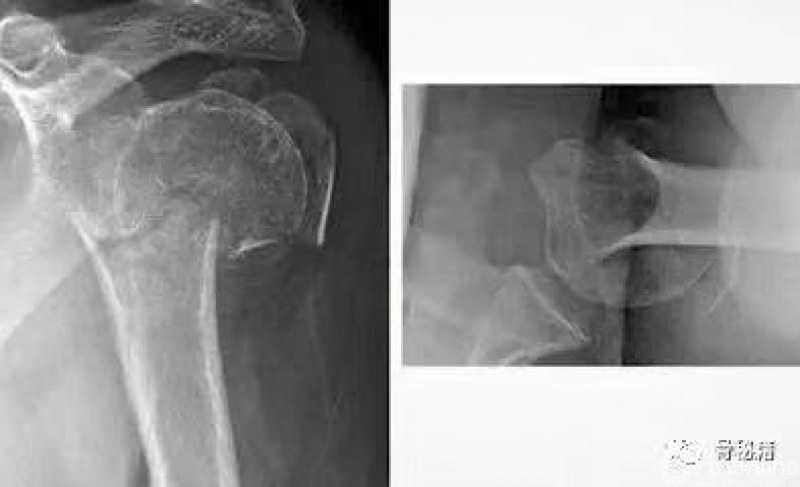

对于老年人来说,骨量也是一个常见问题

直钉对于斜钉来说,其中轴固定的骨量更多,更加稳定一些

这就是为什么multilock 钉子的应用现在这么流行

复位的关键就是将低头的肱骨头敲拨起来,外翻到合适的位置

可以应用摇杆技术等进行肱骨近端的复位,同时需要注意避让进针点的位置

也可以应用鞋拔子来进行翘拨复位,但是需要注意的问题是

外侧骨块必须是完整的,内侧一定要足够深入到头下的位置在骨量较好的地方进行翘拨